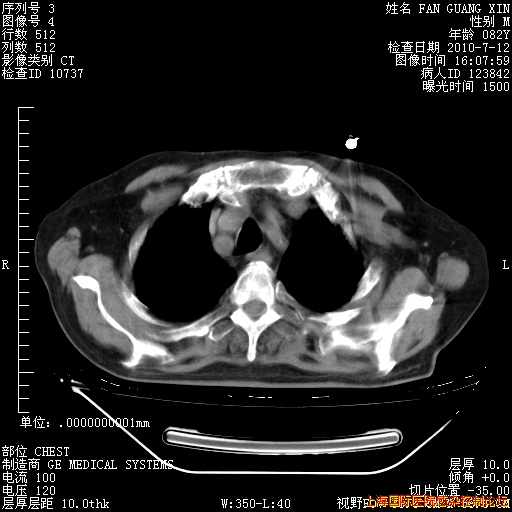

6月12日纵膈窗

回复